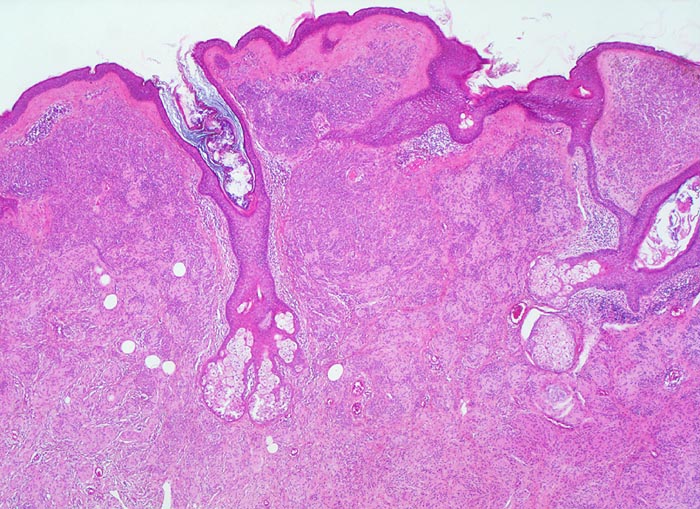

Verlauf: Erworbene Naevi können ein lentiginöses oder ein kongenitales Wachstumsmuster aufweisen (Ausbreitung der Naevuszellen in der tieferen Dermis entlang von Adnexstrukturen). Letzteres bedeutet nicht, dass der Naevus bei Geburt schon bestand. Am Anfang der Entwicklung erworbener Naevi steht die Lentigo simplex ( 5299), welche durch Vermehrung einzeln liegender Melanozyten im Bereich der basalen Epidermis zustande kommt und makroskopisch als scharf begrenzte braune Makula imponiert. Daraus entwickeln sich junktionale Naevi mit Nestern von jeweils drei oder mehr Naevuszellen in der basalen Epidermis ( 5362). Bei Compound Naevi (= dermoepidermaler Naevuszellnaevus) finden sich zusätzlich zu den epidermalen auch intradermal gelegene Naevuszellen oder Nester von Naevuszellen ( 565). Compound Naevi zeigen ein sehr variables makroskopisches Bild von gering erhabenen bis zu polypoiden, gestielten oder verrukösen Läsionen. Die Farbe variiert von braun über grau bis zu hautfarben. Diese Naevi bleiben über Jahre weitgehend unverändert und entwickeln sich schliesslich weiter zu rein dermalen (=corialen) Naevi mit ausschliesslich intradermal gelegenen, oftmals unpigmenierten Naevuszellen, um schliesslich vollständig zu verschwinden.

Kennzeichnend für einen gutartigen Naevuszellnaevus ist dessen Symmetrie und die Ausreifung der intradermalen Naevuszellen von oberflächlich gelegenen grossen, runden, pigmentierten Zellen in grossen Nestern, zu tiefer gelegenen kleineren, runden, nicht pigmentierten, in kleineren Nestern oder einzeln liegenden Zellen und in älteren Läsionen zu spindeligen Zellen mit neuralem Phänotyp mit Verlust der melanozytären Differenzierung (sogenannter Neuronaevus). Gewöhnliche Naevi zeigen keine zytologischen Atypien und die dermale mitotische Aktivität ist minimal.

Die Tumorzellen bilden Nester in der Epidermis und in der Dermis (=dermoepidermaler bzw. compound Naevus).

Die oberflächlichen Naevuszellen zeigen reichlich helles, teils pigmentiertes Zytoplasma und helle ovale Kerne mit kleinen, deutlich erkennbaren Nukleolen. Zur Tiefe hin werden die Naevuszellen kleiner, haben weniger Zytoplasma und dunkle kleine Kerne ohne gut erkennbaren Nucleolus. Die Zellnester werden zur Tiefe hin ebenfalls kleiner (=Ausreifung).